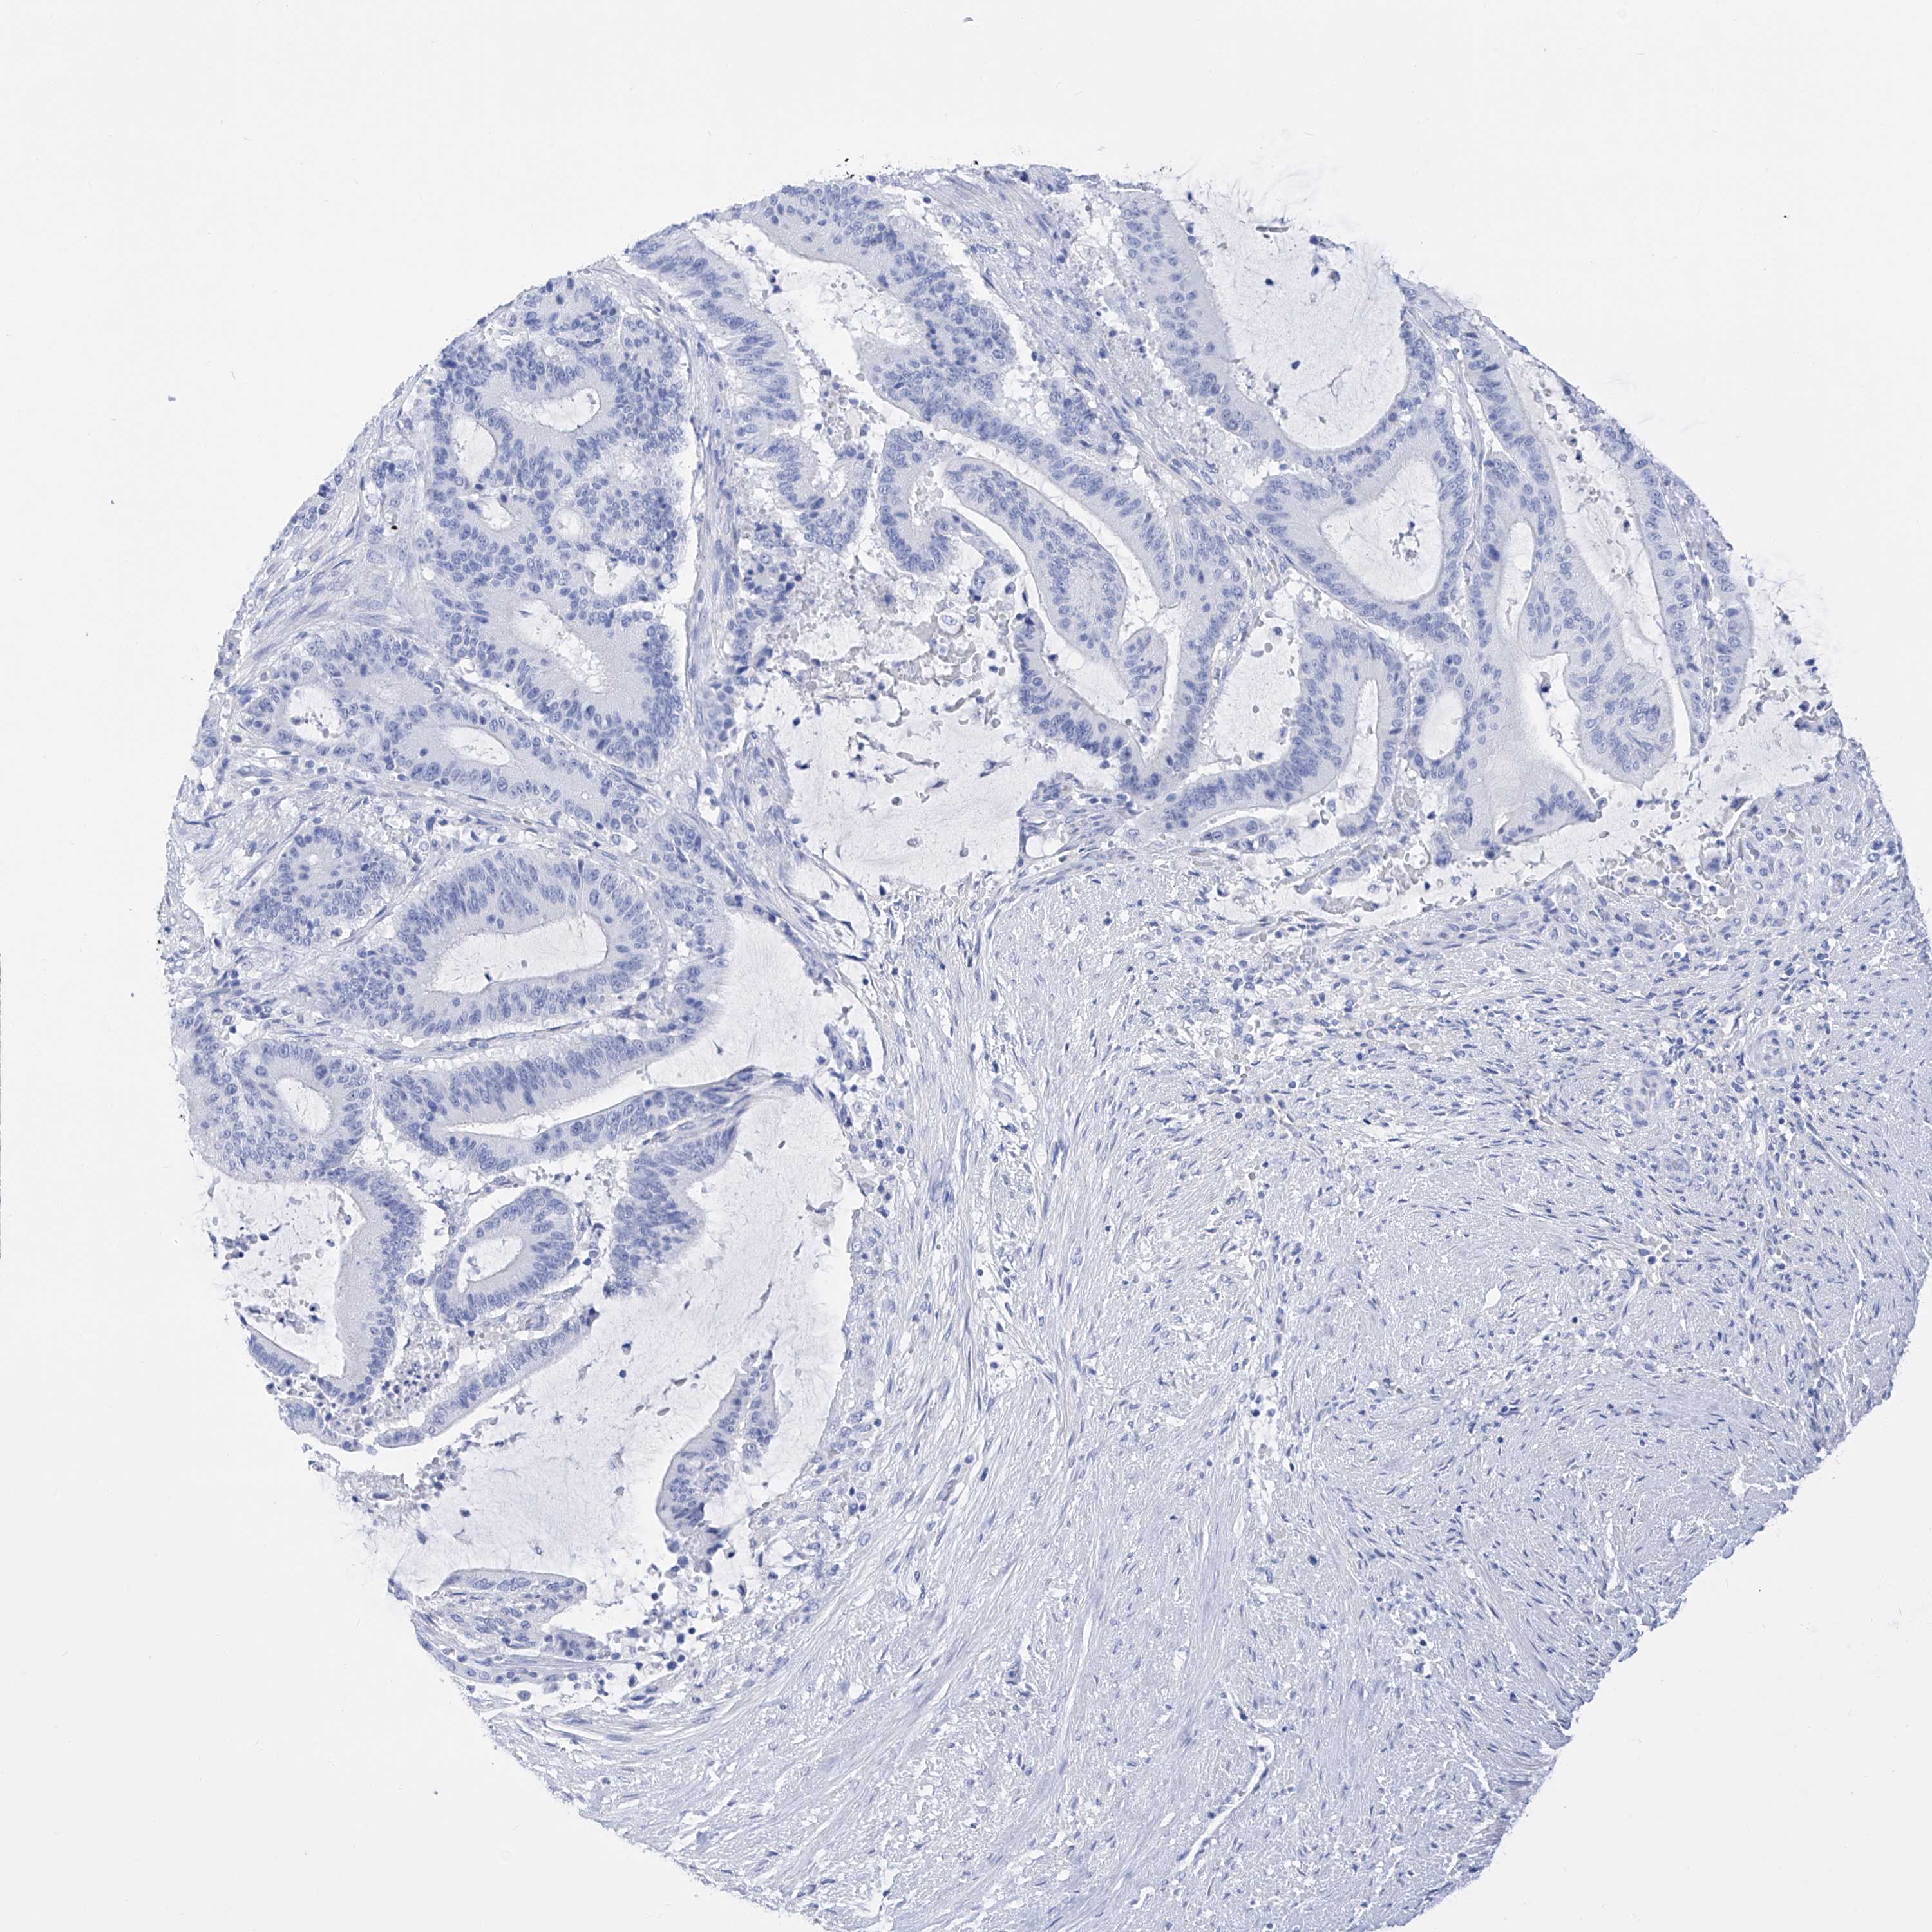

LIVER CANCER - Protein expressioni

A mouse-over function shows sample information and annotation data. Click on an image to view it in a full screen mode. Samples can be filtered based on level of antibody staining by selecting one or several of the following categories: high, medium, low and not detected. The assay and annotation is described here.

Note that samples used for immunohistochemistry by the Human Protein Atlas do not correspond to samples in the TCGA dataset.

Antibody stainingi

Antibody staining in the annotated cell types in the current human tissue is reported as not detected, low, medium, or high, based on conventional immunohistochemistry profiling in selected tissues. This score is based on the combination of the staining intensity and fraction of stained cells.

Each image is clickable and will lead to virtual microscopy that enables deeper exploration of all samples and also displays staining intensity scores, fraction scores and subcellular localization as well as patient and tissue information for each sample.

Antibody HPA030188

Antibody HPA030189

Antibody CAB002210

Staining

High

Medium

Low

Not detected

Intensity

Strong

Moderate

Weak

Negative

Quantity

>75%

75%-25%

<25%

None

Location

Nuclear

Cytoplasmic/membranous

Cytoplasmic/membranous,nuclear

Cholangiocarcinoma

Carcinoma, Hepatocellular, NOS